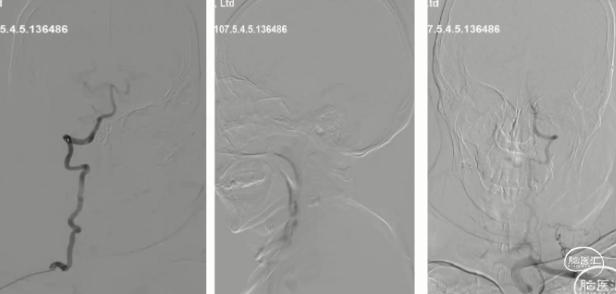

脑血管造影(主动脉弓及左侧颈内动脉2023-06-19):l型弓,左侧颈内动脉未见异常,前交通开放,右侧大脑前通过软脑膜支部分代偿

脑血管造影(双侧椎动脉正侧位):右侧大脑后通过软脑膜支部分代偿

脑血管造影 (右侧颈内动脉正侧位)